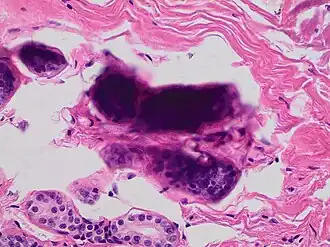

A crush artifact is an artificial elongation and distortion seen in histopathology and cytopathology studies, presumably because of iatrogenic compression of tissues. Distortion can be caused by the slightest compression of tissue and can provide difficulties in diagnosis.[2][3] It may cause chromatin to be squeezed out of nuclei.[4] Inflammatory and tumor cells are most susceptible to crush artifacts.[4]

Crush artifact from compression by forceps on the tissue sample -

Folding artifacts (white arrows) and a crush artifact (black arrow, with cytoplasmic hypereosinophilia and nuclear pleomorphism) from a needle -